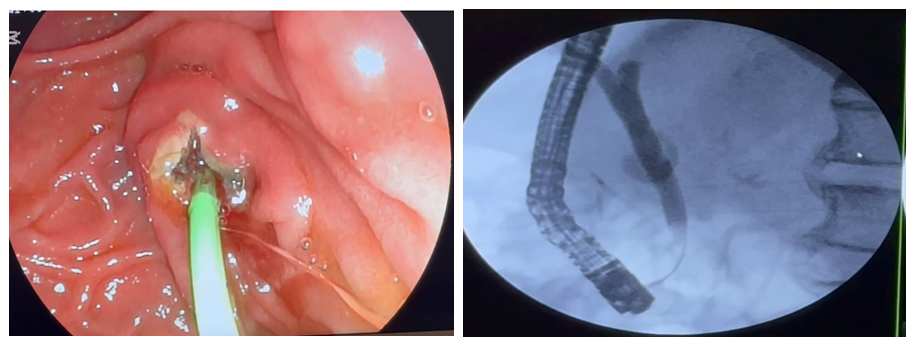

A retrospective analysis of ETI outcomes was conducted in 244 patients from 2022 to 2025. Patients with signs of acute pancreatitis after admission to the clinic were excluded from the study. Although 90% of these patients successfully underwent ETI, halting disease progression and avoiding fatal complications, we excluded them from the study group, as our primary goal was to determine the incidence of acute postoperative pancreatitis specifically after ETI.Given the literature data demonstrating that differences in study groups can influence the assessment of the incidence of acute postoperative pancreatitis, we conducted an analysis in three groups of patients. The first group consisted of 206 (84.7%) patients with complicated cholelithiasis. The second group consisted of 27 (11.3%) patients with malignant obstructive jaundice, recruited for the purpose of bile duct decompression. The third group consisted of 11 (4.0%) patients with jaundice due to benign diseases of the hepatopancreatoduodenal zone.For preoperative prophylaxis, most patients received Contrycal 10,000 IU intravenously. Literary data on the efficacy of Contrycal, a synthetic Sandostatin analogue, are conflicting. Contrycal has been shown to significantly increase basal pressure and the frequency of contractions of the simple medullary sphincter, which leads to impaired outflow through the tubular system. The decrease in pancreatic secretion during octreotide administration may, in itself, negate the rather positive effect. Many authors note that the use of the nonsteroidal anti-inflammatory (NSAID) Diclofenac rectal suppository in combination with a proteolytic enzyme is highly effective in the prevention of acute postoperative pancreatitis. Recently, we have begun using NUC rectal suppositories, and it should be acknowledged that the initial results demonstrate multiple advantages in terms of both efficacy and cost.In addition, to reduce the risk of developing acute postoperative pancreatitis, we comprehensively used various technical and tactical methods of preoperative preparation, performing interventions under intravenous or general combined anesthesia, conducting intensive care in the postoperative period, and, relying on our experience and capabilities (equipment in our arsenal), we improved various technical and tactical methods during surgery and, of course, did not neglect the initiation of conservative treatment for the presence of pancreatitis if our patients had factors confirming pancreatitis before surgery.Avoid unnecessary contrast injection into the GB: Using a soft-tip guidewire to determine the direction of the bile ducts and the Wirsung duct prevents unnecessary contrast injection into the Wirsung duct. When performing CDS cannulation, we precisely check the catheter position to visualize the common bile duct and the direction of the Wirsung duct, thereby preventing approximate contrast injection.Avoiding lengthy attempts at gallbladder cannulation: in the presence of anatomical changes in the duodenal canal area, such as deformity of the descending duodenum, the presence of diverticula, the size and length of the ampulla and longitudinal fold, variations in the duodenal canalization angle, or hemostatic disorders, we prefer to perform atypical EPST layer by layer to gradually prevent tissue differentiation impairment, thereby avoiding lengthy and complex cannulation attempts. In our opinion, the duration and number of gallbladder cannulation attempts should be strictly individualized and as short as possible.Preferring the "CUT" mode when performing EPST: To reduce burn injury to the large duodenal tissue, emphasis should be placed on performing EPST in the "CUT" mode whenever possible. Correct and rational use of this mode significantly reduces bleeding and burns to surrounding tissues, thereby preventing the development of acute postoperative pancreatitis.The use of two wires for prophylactic APP stenting, nasopancreatic drainage, or complex cannulations (Fig. 1). APP prosthetics is performed during prolonged procedures during pancreatic stenosis, in the presence of signs of impaired contrast medium flow from the stenotic papillary system and ducts (Fig. 2), to stop bleeding above the APP, and in the presence of multiple risk factors for acute postoperative pancreatitis. | Figure 1. Cannulation of the gallbladder with a guidewire (wire). Stanling of the APP road |

| Figure 2. To prevent the development of acute pancreatic insufficiency against the background of APP stenting, stenosing papillitis and impaired evacuation of contrast agent into the gallbladder |